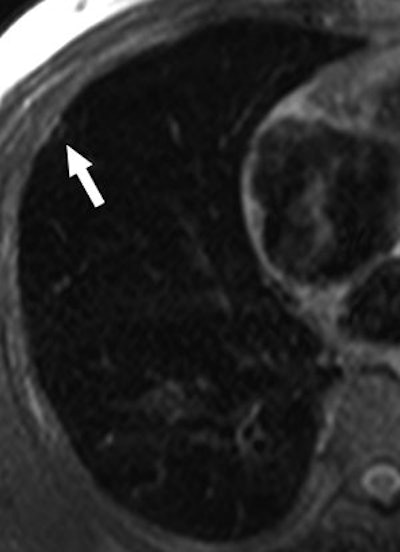

![]() |

| A 68-year-old woman with focal organizing pneumonia in right middle lobe of lung. Above, dynamic MR image before IV injection of gadopentetate dimeglumine. Below, dynamic MR image obtained three minutes after IV injection of gadopentetate dimeglumine shows slightly heterogeneous enhancement that is strongest in early phase (three minutes = time at maximum enhancement ratio). Signal intensity before and three and six minutes (time at maximum enhancement ratio plus three) after contrast injection was calculated by each region of interest. Maximum enhancement ratio, 126%; slope, 42%/min; washout ratio, 15%. |